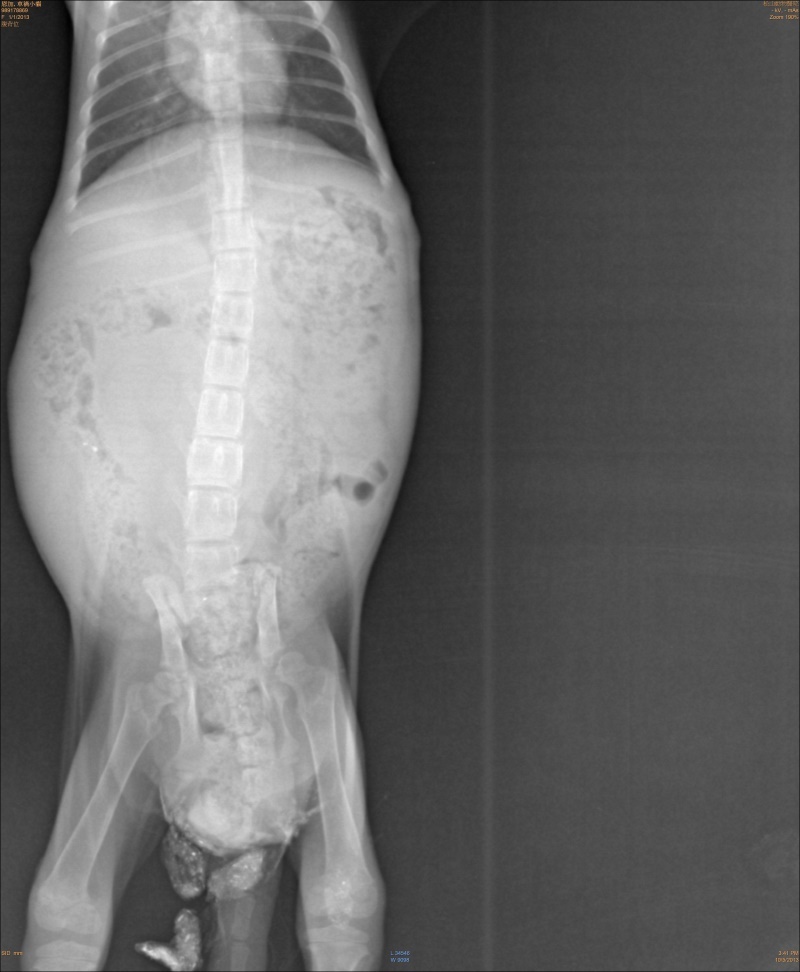

主題: 後肢癱瘓路倒貓 申請者姓名: 岳丹楓 花色: 申請日期: 2013-12-19 20:33:41 申請者部落格: 申請者臉書網址: 所在縣市/合作醫院: 台北市/恩加動物醫院 治療費用: 5700元 需求人數: 13人 已結案 (2014-01-10 17:45:21) 報名人員: Jye Lin x2(已付款)、Jocelyne YuYu Kao x4(已付款)、姆姆媽 x2(已付款)、megumi(已付款)、李仲石 x4(已付款)、 候補人員: 動物病情說明: 一隻在外面路邊爬行的小貓,民眾通報捕捉,送醫檢查為下半身癱瘓,並且積了許多糞便,於是灌腸通便擠尿治療,後肢拖行摩擦破皮有一些小傷口,每天醫師幫小貓擠便和擠尿並給予幫助神經恢復的藥物,經過兩周治療不見改善,狀況穩定,尚未找到可以幫忙照顧的中途,先自費住院,請醫師代為照顧,貓咪驅蟲除蚤後便便正常已經施打預防針(這都是自費),最近找到人可以幫忙,已經先出院,轉由中途照顧,當時的醫療費用還請各位幫忙。